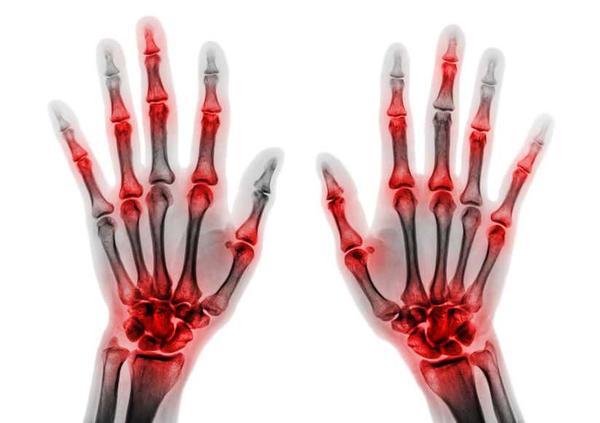

接下来,痛风会从急性发展为间歇发作期,特别是在患者大量酗酒后容易复发,一年内发作次数逐渐增多、病情加重,受累关节可从下肢逐渐发展到上肢、从小关节发展到大关节,在严重情况下甚至是会影响脊椎、肩部关节。

4、痛风石:痛风石分为皮下和慢性痛风石两大类,前者容易出现在患者耳廓、小关节区域,在这些区域可出现大小不一的赘生物、呈现出黄白色,在溃烂之后有白色糊状物排出。

而后者则是尿酸盐结晶沉积在关节、周围组织造成的。无论哪一种痛风石,都会对关节骨质造成损伤,导致周围组织纤维化,甚至是诱发关节畸形、功能障碍。